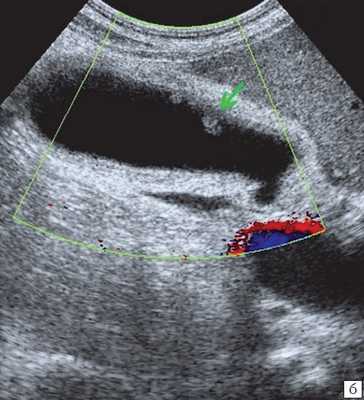

(Левый) На поперечном УЗ срезе через левую долю печени по ходу желчных протоков определяются множественные линейные эхогенные зоны, некоторые из них отбрасывают акустическую тень; такая картина отражает наличие газа в желчных протоках.

(Правый) На поперечном УЗ срезе через левую долю печени визуализируются линейные эхогенные очаги, отбрасывающие «грязную» акустическую тень; такие изменения вызваны наличием газа во внутрипеченочных желчных протоках.